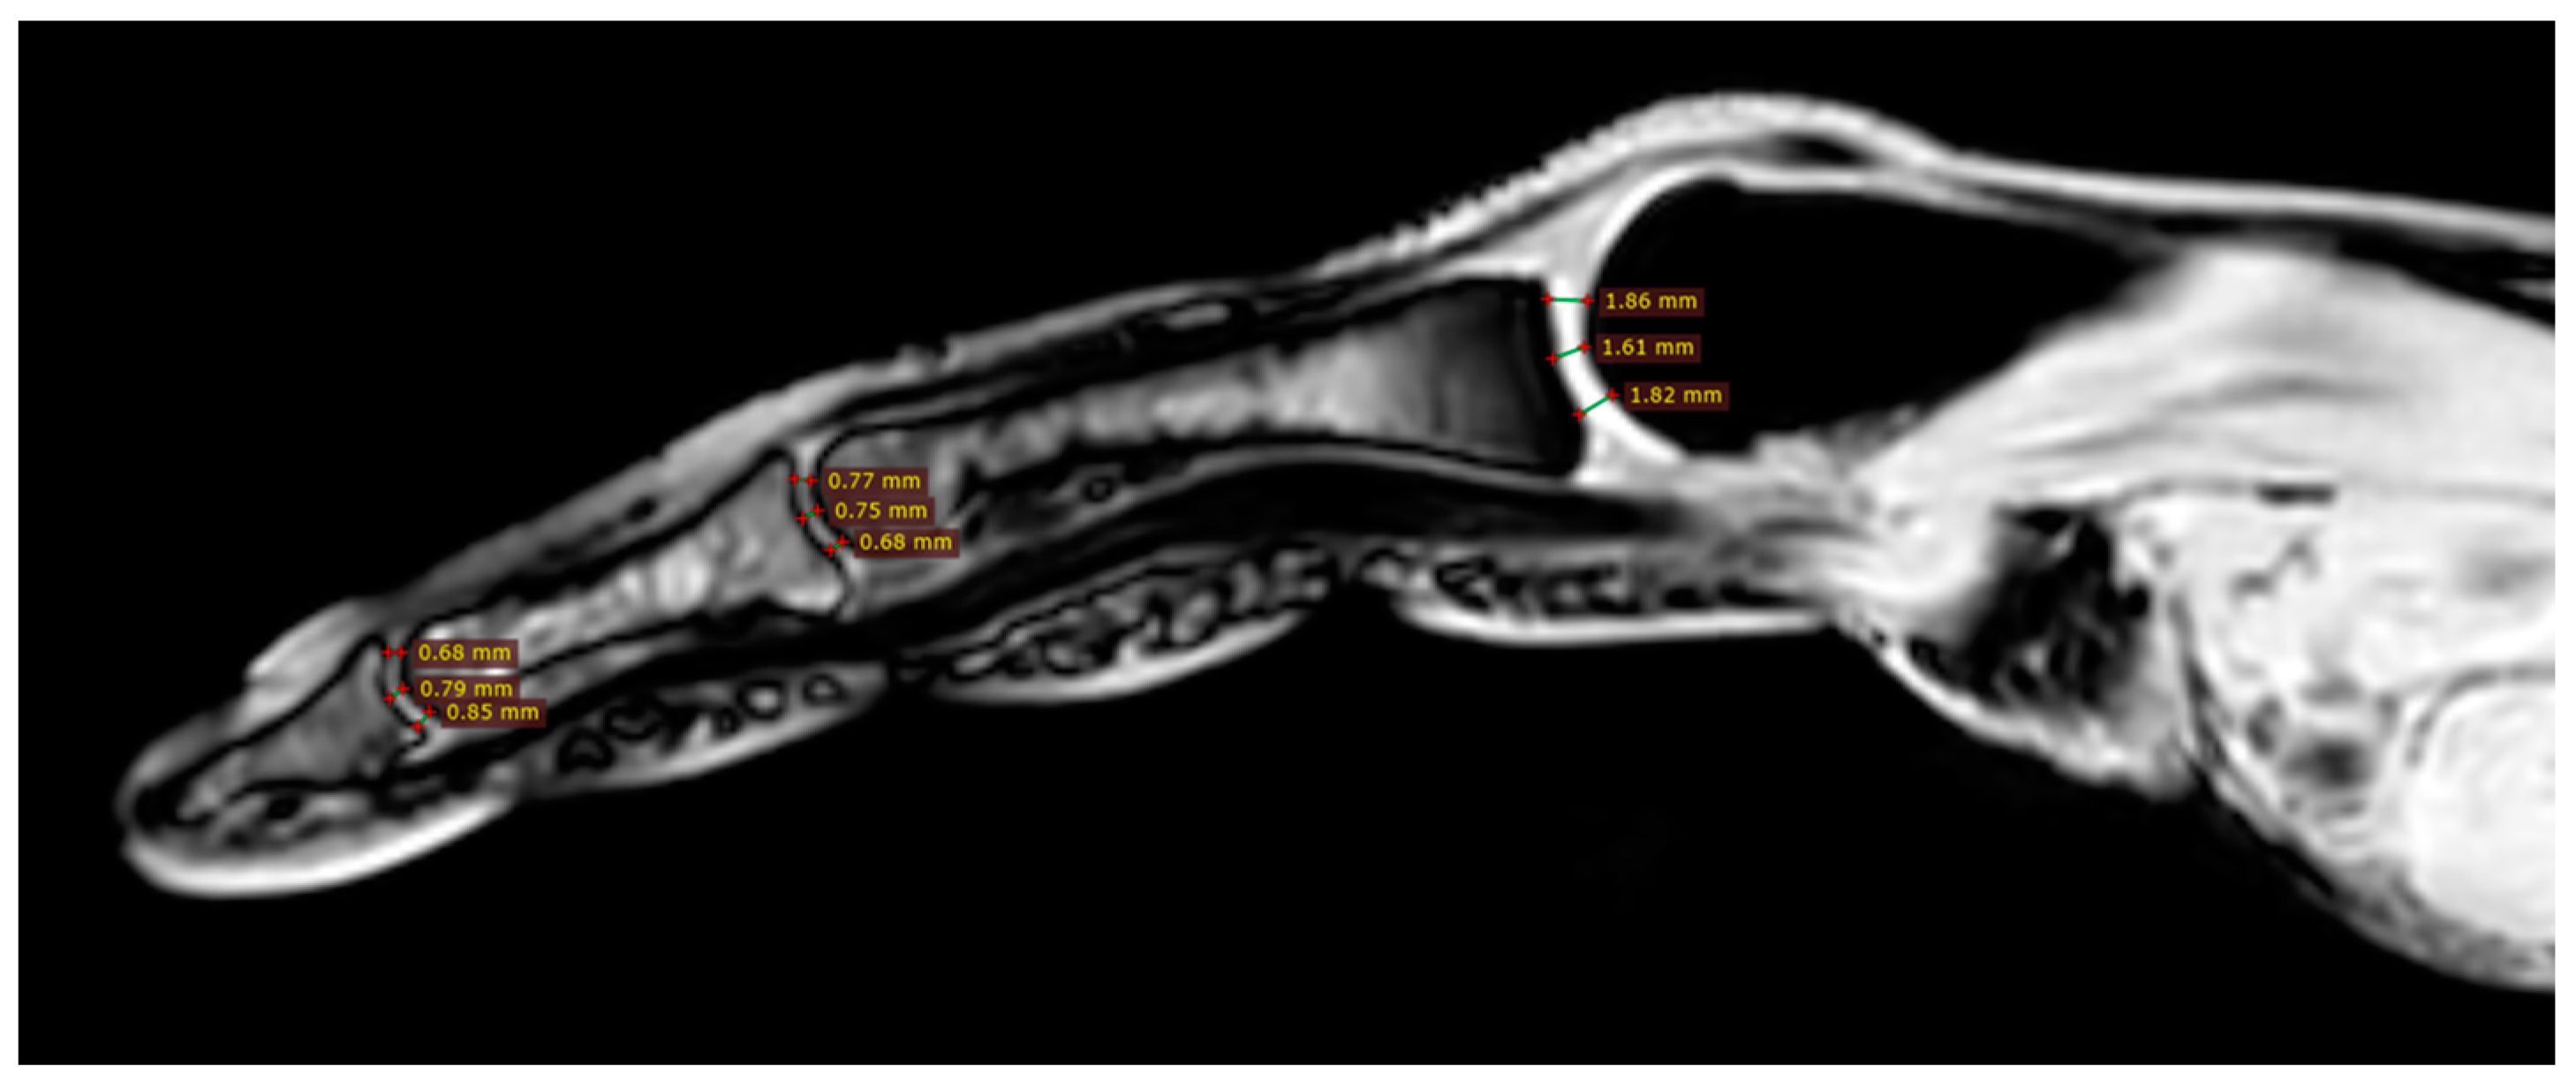

All participants were examined with the three-dimensional quantitative MRI (3D q-MRI). The Philips 3T scanner was used with the coil for small parts. After obtaining structural T1 and T2 scans, the WATS 3D sequence was performed. The WATS sequence is dedicated to the cartilage evaluation and highlights the subchondral cortical layer. Due to the application of a 3D sequence, we were able to obtain the true sagittal cross-section of each finger (Figure 3). This was vital because, in some patients, contractions did not allow for anatomical position of fingers during examination. After adjusting the planes, we measured the distance between two cortical layers for each finger joint in its middle transverse dimension, obtaining three measurements (in volar 1/3, dorsal 1/3, and middle 1/3) and calculating a mean (Figure 4 and Figure 5). The distal phalanx length (DPL), the cartilage thickness of distal interphalangeal joints (DIPJ), proximal interphalangeal joints (PIPJ), interphalangeal joint (IPJ), and metacarpophalangeal joints (MCPJ) in all participants were measured.

Figure 4.

Three measurements of cartilage thickness in each finger joint (in volar 1/3, dorsal 1/3, and middle 1/3)—finger without acro-osteolysis.

In general comparison, there was no significant difference in all evaluated parameters. The same was for the comparison of parameters between fingers of the same hand (DPL p = 0.2925, DIPJ p = 0.1800, PIPJ p = 0.0898; MCPJ p = 0.1893; pulled data from both groups, Table 2) and for the comparison of cartilage thickness within joints of fingers 2–5. (finger 2. p = 0.6958; finger 3. p = 0.6857, finger 4. p = 0.2646; finger 5. p = 0.5122; pulled data from both groups, Table 2). In finger 1, the cartilage of MCPJ was significantly thicker than that of IPJ (p = 0.0005).

Despite the insignificant results above, we noticed that joint cartilage is thinner in fingers with acro-osteolysis (Figure 4 and Figure 5). In the PIP joint of fingers with acro-osteolysis, the mean cartilage thickness was 0.5 mm (p = 0.0043). In the DIP joint of fingers with acro-osteolysis, the mean cartilage thickness was 0.4 mm (p = 0.0034). In the MCP joint, we did not find a statistically significant difference between the study and control group (p = 0.8554). In Table 3, there is a comparison of parameters between these fingers and all the rest from both groups.